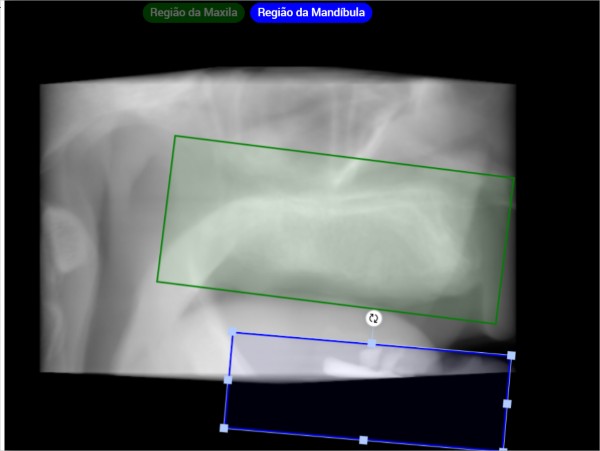

🛠️ Ajuste Manual do Arco Dentário

Normalmente não é necessário, mas você pode fazer o ajuste manual quando:

-

há baixa qualidade de imagem

-

há muitos metais

-

o paciente é edêntulo

-

apenas parte da arcada aparece

Você pode:

-

Abrir o Ajuste de transaxiais

-

Marcar manualmente a posição central da arcada

-

Ajustar a inclinação

-

Deixar a IA recalcular os cortes

🧩 Quando o exame mostra só uma arcada

Exemplo: o exame mostra só maxila, mas a IA tenta marcar maxila + mandíbula.

✔ Como corrigir

-

Clique em Editar arco dentário

-

Selecione Apenas a Maxila

-

O sistema recalcula e corrige tudo automaticamente

Isso também vale para o inverso (Apenas Mandíbula).